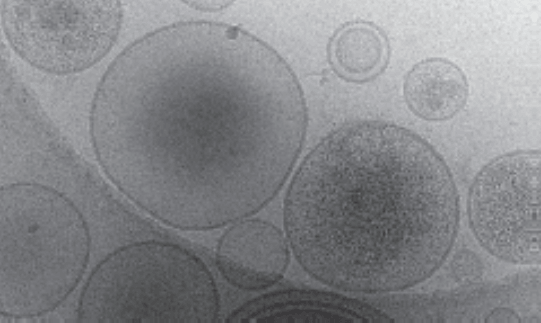

Cryo-electron microscopy image of EVs extracted from human ovarian cancer cells

Figure: Heterogeneous EVs. Cryo-electron microscopy image of EVs extracted from human ovarian cancer cells. Even EVs extracted from a single clonal cell line exhibit heterogeneity in both size and their molecular cargo.